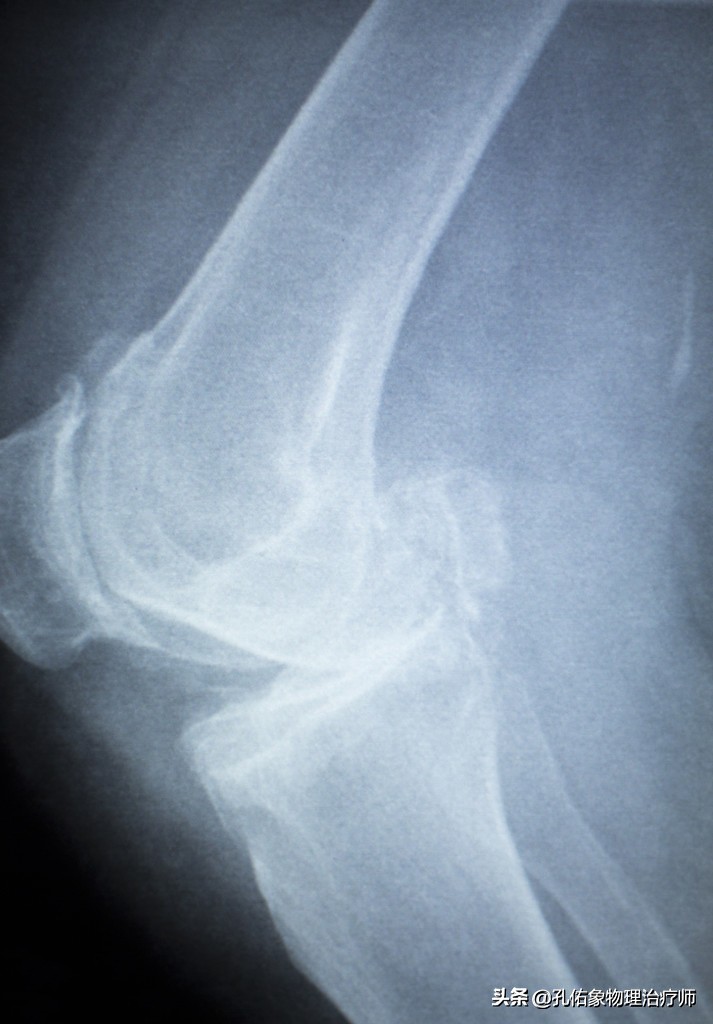

然而却忽略了半月板的问题,任其发展,继续忍受着疼痛做自己的事情,直到坚持不住了,没办法忍受疼痛时,才会来医院看膝关节究竟是怎么了?结果一拍片,就是下面这种状态。

半月板损伤了,会有什么样的结局?

或许有些年轻人有过半月板损伤的经历,有的是选择保守治疗,有的是选择手术治疗,还有就是老年人,基本忽略了半月板的问题,任其发展。究竟它会对我们人体造成什么样的影响呢?

半月板若是损伤后,不经过正常精准的治疗,一定会出现撕裂的那侧膝关节疼痛,特别是在下蹲或是上下楼的时候,疼痛更为明显。它会激发身体在行走时应力的刺激,影响到滑膜,出现膝关节积液肿胀。甚则会出现因损伤,不能很好的匹配膝关节的运动而出现交锁卡住的情形。